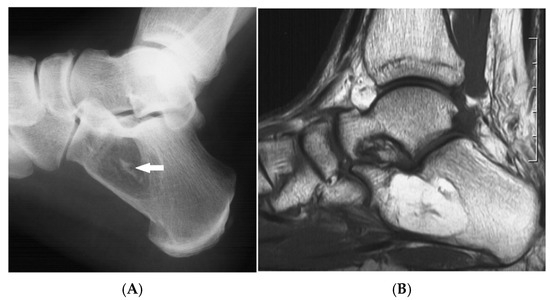

Figure 3.

Intraosseous lipoma, calcaneum. (A) Plain radiograph demonstrating the classic location of the lesion with “bull’s eye” sign (solid white arrow). (B) Sagittal T1W MRI with fat-containing lesion.

Advanced stages of the lesion may show central or peripheral calcification, described as a distinctive “bull’s-eye” appearance, or ossification, occasionally mimicking enostosis, chondroid lesions, or osteonecrosis. Asymptomatic lesions require no treatment, whilst symptomatic cases may be treated with curettage and bone grafting. Recurrence and malignant transformation are rare.